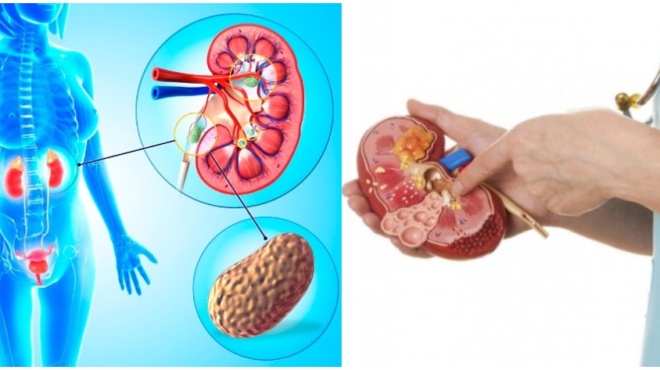

Πέτρες στους νεφρούς – Συμβουλές για την υγεία: Τροφές που αποτρέπουν τις πέτρες

Επειδή οι πέτρες στους νεφρούς ποικίλλουν ανάλογα με το από τι είναι φτιαγμένες, οι τροφές, που περιλαμβάνονται σε ένα σχετικό διατροφικό πλάνο, θα διαφέρουν. Ο καθένας πρέπει να μιλήσει με το γιατρό του για το ποιες τροφές μπορεί να του/της προκαλούν πέτρες, για να τους βοηθήσει ο γιατρός να καθορίσουν τι πρέπει και τι δεν πρέπει να τρώνε για να αποφύγουν το σχηματισμό λίθων στο μέλλον.

Τα παρακάτω είναι μερικές προτάσεις για το τι πρέπει να συμπεριλάβετε σε μια διατροφή για να μην έχετε ποτέ πέτρες στους νεφρούς.